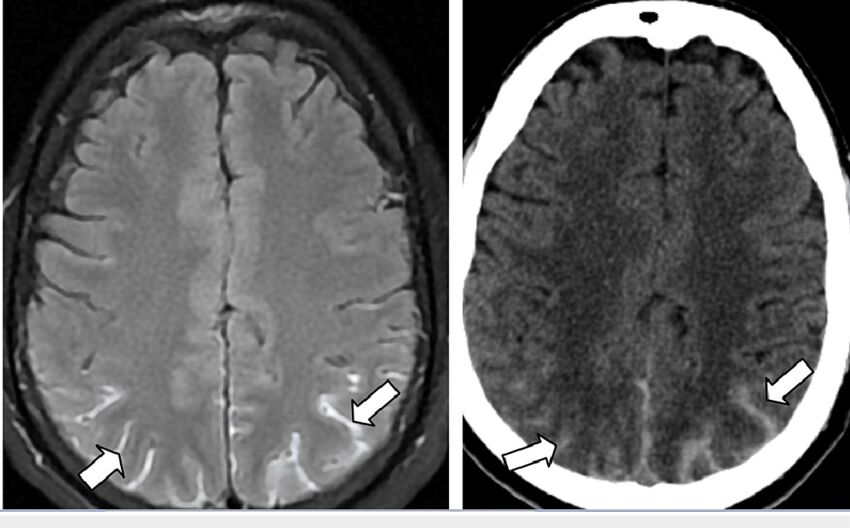

(D) 蜘蛛膜下腔出血

蛛網膜下血腫subarachnoid hematomas長這樣